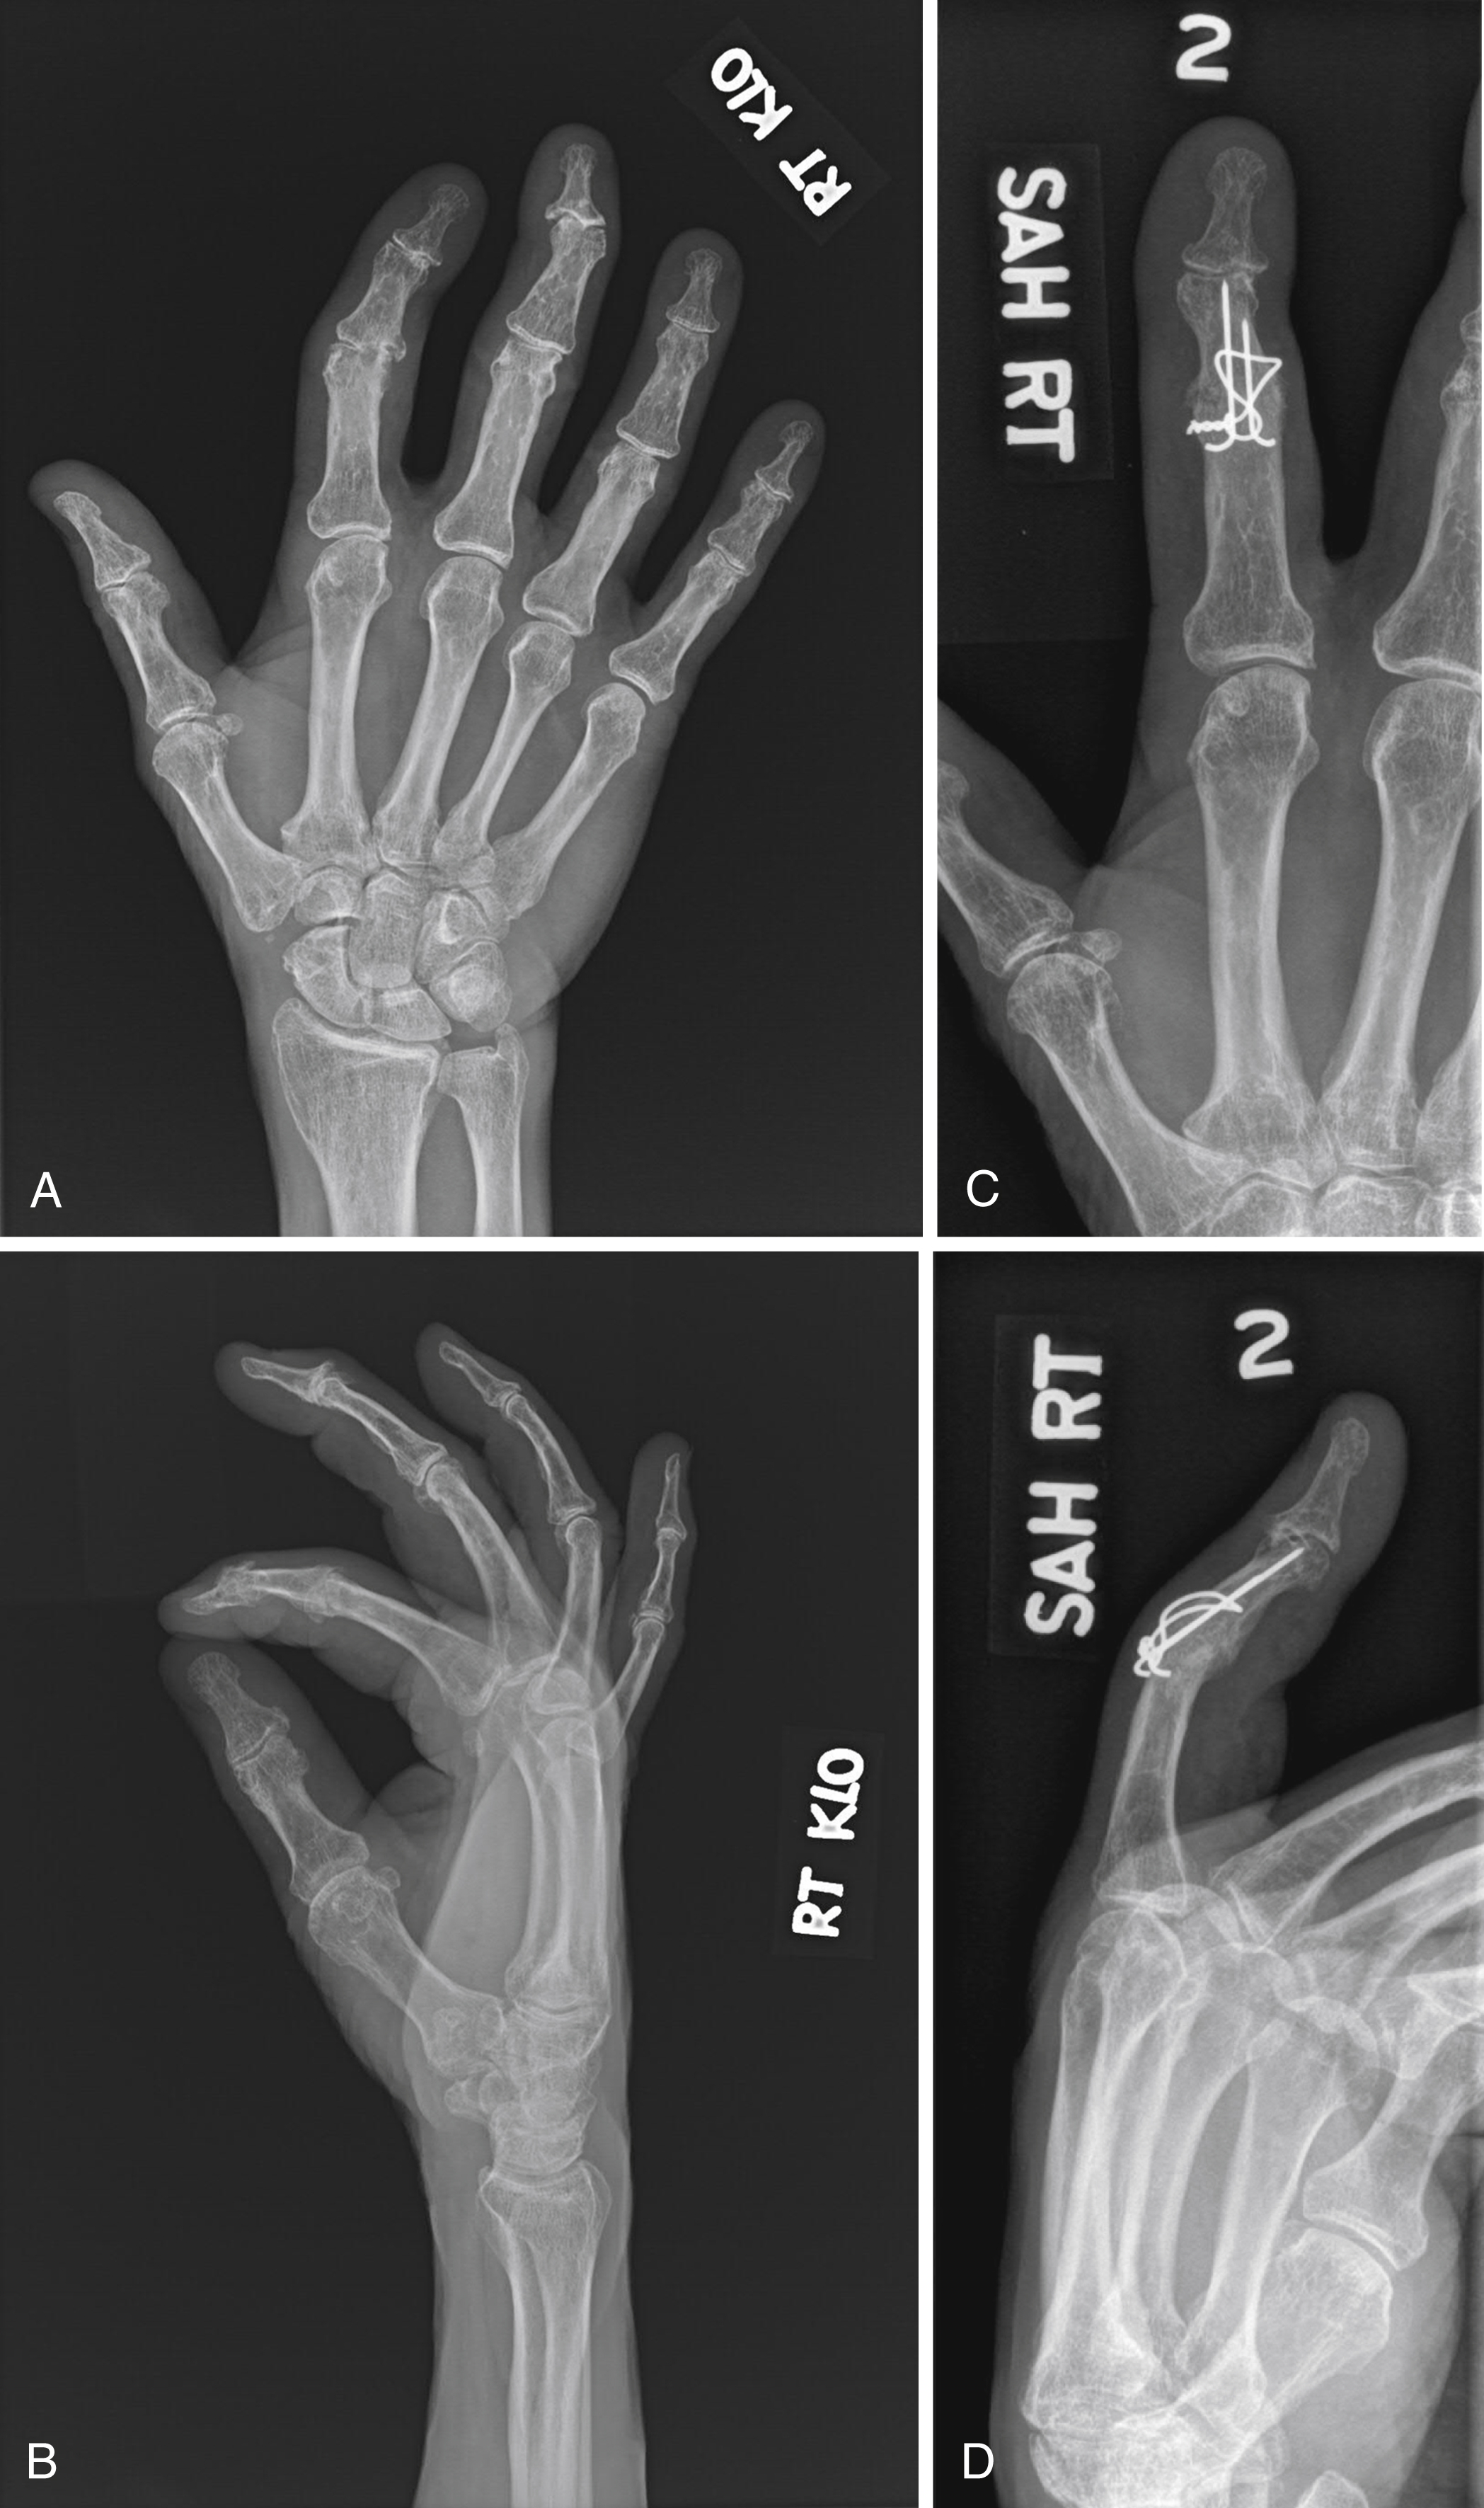

The procedure can be performed under regional or general anesthesia. Through a skin H incision, the terminal tendon is transversely incised, and the joint is exposed. Using a rongeur or a 2-mm high-speed bur, the articular cartilage is denuded, and a flush contact surface is created. Either K-wires, K-wires with a surgical steel wire loop or a headless variable pitch compression screw ( Fig. 57.1 ) can be used to achieve appropriate fixation. Care is taken to avoid inside-out injury of the nail bed which may lead to nail plate deformity. Complications include infected and aseptic nonunions, nail deformity, and prominent hardware distally at the tip of the finger.

K-wire figure-of-8 tension band wire technique is generally preferred. The degenerative articular surfaces of the PIP joint are osteotomized. The osteotomy of the middle phalanx articular base is performed perpendicular to the long axis of the bone while the osteotomy of the head of the proximal phalanx is done at a progressive angle (30, 40, 50 or 60 degrees) for the index, long, ring or small fingers, respectively. Two parallel 0.035-inch K-wires are drilled first in a retrograde fashion perpendicular to the osteotomy cut of the proximal phalanx then in an antegrade direction across the osteotomized surface of the middle phalanx. The tips of the K-wires should stop about 5 mm shy of the distal articular aspect of the middle phalanx for later advancement. Once the articular surfaces are stabilized, another 0.035-inch K-wire is drilled transversely to the axis of the middle phalanx through the dorsal cortex at the junction of the proximal and middle thirds of the shaft. A figure-of-8 loop using a 20G surgical steel wire is passed through the drill hole in the middle phalanx shaft then just proximal to the K-wires exiting the proximal phalanx. Next, the exposed K-wires are cut approximately 1 cm superficial to the dorsal cortex of the proximal phalanx and are bent 90 degrees to capture and secure the figure-of-8 wire loop after the wire loop has been tightened down by twisting with a needle driver or needle nose pliers. The twist of the figure-of-8 wire is then cut and gently driven down over the middle phalanx with a small bone tamp and mallet ( Fig. 57.2 ). Complications of the figure-of-8 tension band arthrodesis technique for the PIP joint include nonunion (3%), malunion (1%), hardware prominence (9%), phalangeal fracture, hardware failure, and skin necrosis (3.5%). ,